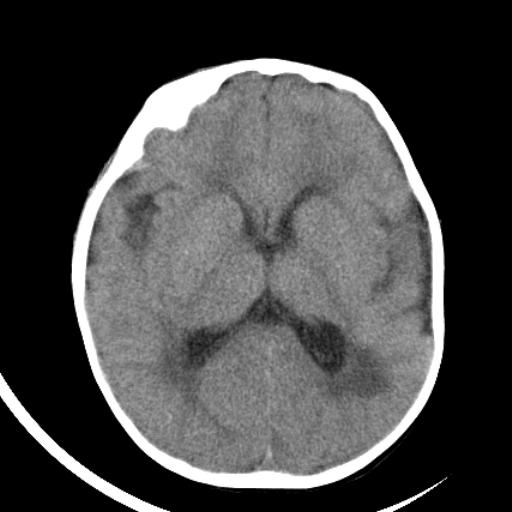

双侧脑室前后角周围白质片状低密度影,双侧侧脑室旁、双顶叶皮层及皮层下多个小原点状钙化灶,不除外torch感染。右顶叶脑回似乎较对侧大,建议mri检查以除外脑发育异常。

考虑:1、巨脑回畸形(皮质明显增厚+脑回明显增宽+白质减少)。

2、torch综合征(室管膜下钙化+白质内及皮髓质交界处多发钙化)。